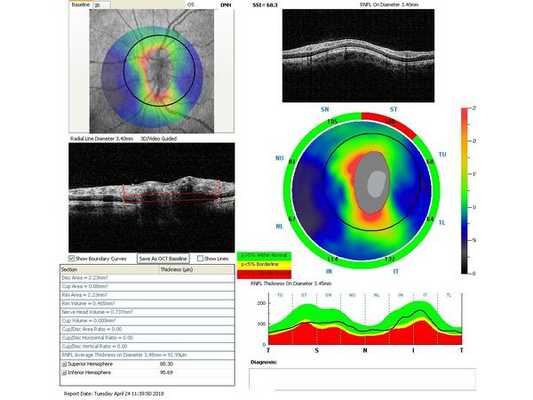

Гониоскопия выявила, что угол передней камеры глаза открыт, профиль радужки плоский, в углу передней камеры по всей окружности визуализируется резидуальная ткань, похожая на пигментированные отростки корня радужки. Она доходит до трабекулярной зоны. Также при первичном осмотре была проведена оптическая когерентная томография (ОКТ)(рис. 1-4).

Через неделю и через месяц после операции пациентка приходила на осмотры для проверки внутриглазного давления, остроты зрения и проведения ОКТ (рис. 5-8). Результаты обследований через месяц после лазерного лечения: ⠀•⠀Острота зрения: ⠀⠀⠀OD: 0,1 sph -2,0 cyl -0,75 ax 85 = 1,0; ⠀⠀⠀OS: 0,1 sph -2,5 cyl -0,75 ax 95 = 1,0. ⠀•⠀Поля зрений - без изменений. ⠀•⠀Тонометрия обоих глаз по Маклакову - 21 мм рт. ст. (без капель). ⠀•⠀Гониоскопическая картина без изменений.